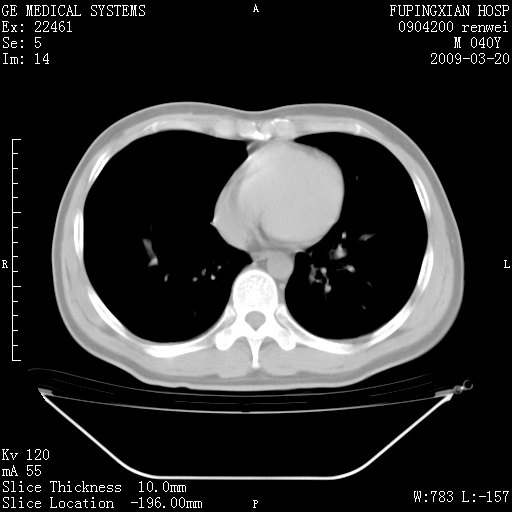

标题: CT18920:平时体健,体检时发现以下问题。 [打印本页]

标题: CT18920:平时体健,体检时发现以下问题。

右肺气肿。

右肺局限性肺气肿

右肺局限性肺气肿。

右肺局限性肺气肿,有无呛咳史?

右肺局限性肺气肿;[考虑黏液栓]所致。

右肺局限性肺气肿,原因?先天支气管闭锁?粘液栓?